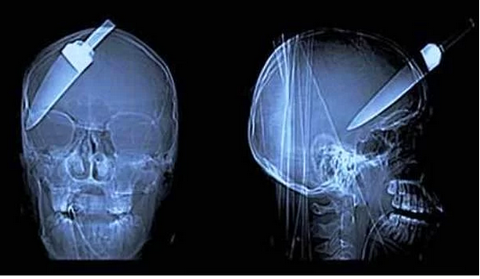

Galerinin tamamı için tıklayınızKafaya saplanan bıçak

Silahlı soygun kurbanı bu arkadaş, tamamen iyileşmiş

Kafaya saplanan bıçak